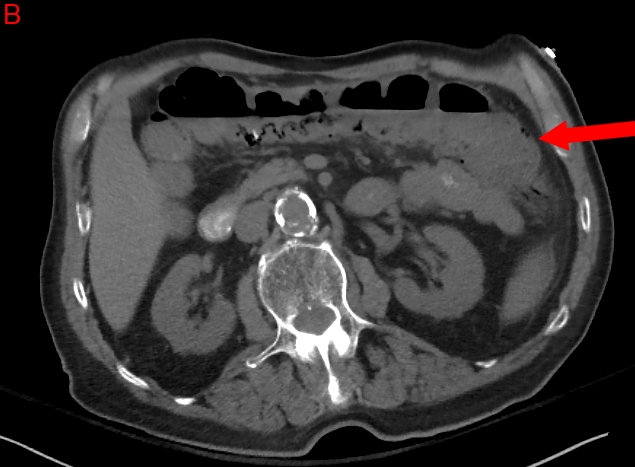

The abdominal aorta is the most common site of an arterial aneurysm. Abdominal aortic aneurysms (AAA) are usually located below the renal artery (infrarenal aorta).

The abdominal aorta is 1-3 cm in diameter in most individuals, and a diameter >3 cm at the level of the renal arteries is considered to be an aneurysm. Unlike thoracic aortic aneurysms, an AAA involves all aortal layers and does not create an intimal flap or false lumen. An AAA typically occurs in people aged >60 years and occurs at a higher rate in smokers, men, and people with a history of coronary artery disease.

Symptoms

Patients typically have few symptoms with AAAs, which are usually incidentally found on screening ultrasound or CT scan of the abdomen. Physical examination can reveal a pulsatile abdominal mass at or above the level of the umbilicus. Once the aneurysm ruptures, only about 50% of the patients survive to come to the hospital. They present with profound hypotension, abdominal or back pain followed by syncope, and possible pulsatile mass on examination. An AAA can rupture into the retroperitoneum and create an aortocaval fistula with the inferior vena cava, leading to venous congestion in retroperitoneal structures (e.g. bladder). The fragile and distended veins in the bladder can rupture and cause gross hematuria (as in this patient).

The symptoms and signs can also mimic other abdominal pathologies, such as renal colic, mesenteric ischemia, pancreatitis, diverticulitis, and biliary disease. This patient's acute onset of symptoms, age, and profound hypotension suggest ruptured AAA, which must be ruled out before the other etiologies. He should be immediately taken to the operating room for emergent surgical repair of the ruptured AAA. Mortality with this condition is approximately 50%, so early recognition and operative intervention is essential.